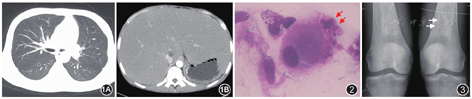

患者男,25岁,因"发现脾大17年,喘憋、皮肤黄染3月,加重1个月"于2018年6月3日入住北京协和医院全科医学科(普通内科)。患者8岁起家人发现磕碰后易出现鼻衄及皮肤瘀斑,外院查体发现脾大。外院查血常规:白细胞及血小板计数轻度降低,肝功能未见异常。行骨髓穿刺活检:粒系增生欠活跃,巨核细胞以颗粒巨核细胞为主,余未见明显异常。诊断考虑"原发性巨脾",予行脾切除术,术后病理提示不能除外肉芽肿性病变。监测白细胞及血小板计数恢复正常,未进一步诊治。2018年2月患者自觉活动耐量明显下降,步行300 m即出现喘憋,夜间需高枕卧位。同时皮肤黏膜及巩膜出现黄染,伴皮肤瘙痒,否认骨痛。查血常规:白细胞23.37×109/L,血红蛋白78 g/L,血小板71×109/L;尿常规:尿蛋白(-);肝功能:白蛋白23.65 g/L,丙氨酸转氨酶(ALT)134 U/L,总胆红素67.75 μmol/L,直接胆红素39.04 μmol/L,γ谷氨酰转肽酶128 U/L;肾功能:未见异常。血氨44.9 μmol/L。乙型肝炎五项、抗丙型肝炎病毒抗体、巨细胞病毒IgM抗体及嗜异性凝集试验均(-);血CA19-9、甲胎蛋白均(-)。胸腹部CT:双肺透亮度减低,余未见明显异常;肝肿大明显(图1)。超声心动图检查:射血分数66%,轻度三尖瓣反流伴中度肺动脉高压,轻度肺动脉瓣反流,全心增大,心包少量积液。外院予以保肝、利尿治疗后呼吸困难症状略有改善。遂于2018年6月3日为进一步诊治收住本院。患者病程中否认口腔及外阴溃疡、皮疹、关节肿痛、雷诺现象等症状。既往体格发育较同龄人迟缓,但学习成绩中上等,无明显活动耐量减退,上大学期间自述可与同龄人进行同样强度长跑活动,但不喜好剧烈运动。起病以来,睡眠欠佳,大小便正常。幼时脾切除手术期间曾输血支持,余既往史和家族史均无特殊。

入院后完善检查:尿常规+沉渣:尿蛋白微量,红细胞25个/μl;24 h尿蛋白:0.4 g/24 h。肝功能:白蛋白27 g/L,ALT 17 U/L,总胆红素97.2 μmol/L,直接胆红素74.8 μmol/L,γ谷氨酰转肽酶105 U/L。红细胞沉降率86 mm/1 h;超敏C反应蛋白、抗核抗体谱、自身免疫性肝炎抗体谱、抗心磷脂抗体、抗中性粒细胞胞质抗体、补体均(-);免疫球蛋白G:27.9 g/L,免疫球蛋白A:9.74 g/L;人免疫缺陷病毒抗体、快速血清反应素环状卡片试验(-);巨细胞病毒-DNA<500拷贝/ml,Epstein-Barr病毒-DNA<500拷贝/ml;降钙素原、血结核感染特异性T细胞检测、嗜异性凝集试验、布氏杆菌凝集试验、G试验均(-)。血气分析(未吸氧):pH 7.47,二氧化碳分压21 mmHg,氧分压62 mmHg,血浆碳酸氢根浓度15.3 mmol/L;肺功能:限制性通气功能障碍伴弥散功能减低。计算机断层摄影肺血管造影(CTPA):未见肺动脉栓塞表现。超声心动图检查:射血分数58%,轻度三尖瓣反流伴中度肺动脉高压,轻度肺动脉瓣反流,全心增大,心包少量积液。心脏对比增强超声:可见右心房出现气泡后第4个心动周期左房出现气泡,考虑存在肺内分流。骨髓穿刺涂片:粒系以中性分叶核粒细胞比例增高,达34%,余各阶段比例及形态大致正常。红系晚幼红细胞为主,余各阶段比例减低。红细胞大小不等,部分中心淡染区扩大。淋巴细胞及单核细胞比例形态正常。全片未见巨核细胞,血小板少见。可见戈谢细胞(图2)。骨髓活检:骨髓中纤维组织明显增生,仅见极少许造血细胞,未见巨核细胞。网织红细胞(+)。患者入院后体温正常,夜间仍无法平卧,干咳明显,余无其他不适主诉。自然状态下指氧饱和度波动于71%~80%,吸氧6 L/min,可达86%~93%。经多学科会诊考虑患者幼年起病,以不明原因脾大为突出首发表现,骨髓穿刺涂片发现戈谢细胞,考虑戈谢病可能性大。应进一步进行酶活性检测明确诊断。患者目前突出症状为呼吸困难,血气评估为Ⅰ型呼吸衰竭,CTPA未见肺栓塞,心脏对比增强超声明确存在肺内分流,结合肝脏情况,诊断考虑继发肝肺综合征。后完善β-葡糖苷酶1.9 nmol·h-1·mg·Pr-1(6.5~20.6 nmol·h-1·mgPr-1)。骨扫描:双侧第8后肋异常所见,考虑为良性病变可能性大,余骨骼未见明显异常。膝关节相:双侧股骨下端内侧骨质密度不均匀增高(图3)。建议患者开始伊米苷酶替代治疗,患者及家属讨论后因经济等方面原因拒绝替代治疗方案,返家后继续氧疗支持。2019年10月电话随诊,患者出院半年后因继发肺部感染死亡。最终诊断:戈谢病、肝肺综合征、Ⅰ型呼吸衰竭、肺动脉高压、骨髓纤维化。

在戈谢病患者中,骨骼受累是主要的临床特征之一,但骨髓纤维化罕有报道。影像学表现包括弥漫性骨质疏松、病理性骨折及骨质破坏,其中以股骨与骨盆最为常见,长骨改变以双侧股骨中下段对称性增宽,似啤酒瓶样改变最为特征。其机制尚未明确,目前怀疑戈谢细胞浸润。从机制上,戈谢病患者受累骨骼内可出现骨密度减小、骨髓浸润和骨梗死等病理改变。另外,在戈谢病体外模型中,原始造血和间充质祖细胞的增殖受损,提示有固有缺陷的参与[3,4]。如图3所示,确实发现有双侧股骨下端内侧骨质密度的不均匀增高,并且骨髓活检提示骨髓纤维化,但这些并非戈谢病典型的骨和骨髓的常见受累表现,未来尚需更多病例的总结和观察。